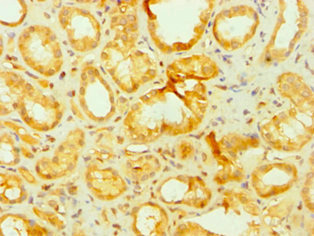

Immunohistochemistry of paraffin-embedded human kidney tissue using CSB-PA001912DSR2HU at dilution of 1:100